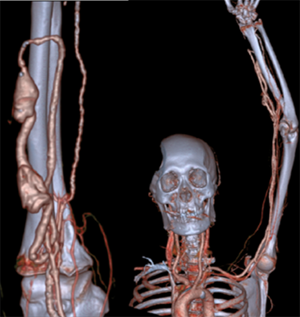

张东亮主任耐心听完患者的叙述,给出了诊断:“肿胀手综合征”。肿胀手的主要原因是自体动静脉内瘘成型后,静脉发生动脉样改变,管腔内静水压力升高,当静脉血液回流不畅时就会导致压力进一步升高,从而形成患侧手臂显著增粗的病症,这在起搏器植入的血透患者中,发生率更高。张主任立刻为老李安排检查:首先是超声明确内瘘吻合口内径,发现血管流量尚可,静脉弓汇入锁骨下静脉处相对性狭窄伴迂曲。随后又进行了上肢及深静脉CT三维重建(CTA+CTV),发现主要病变为锁骨下静脉汇入头臂静脉处静脉瓣增生狭窄(如下图)